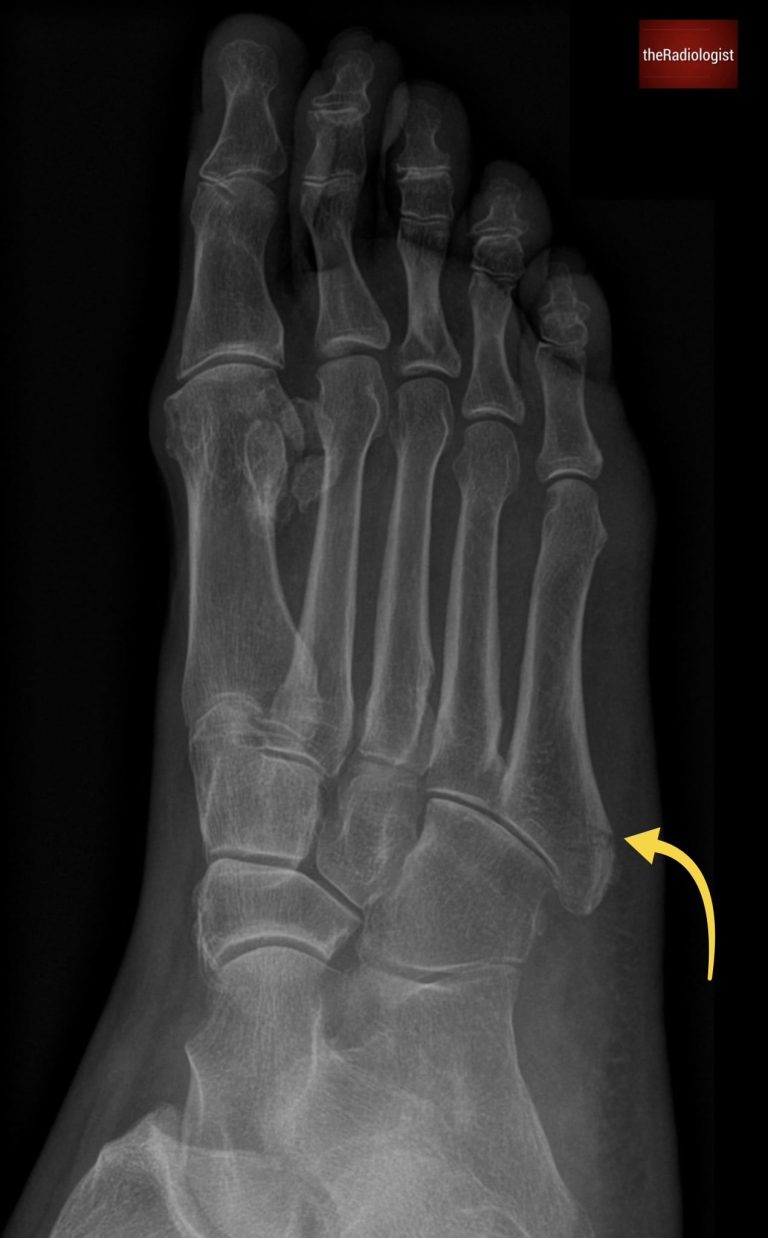

Always scrutinise the fifth metatarsal and in particular the base. Here there is a transverse lucency in keeping with a Jones fracture.